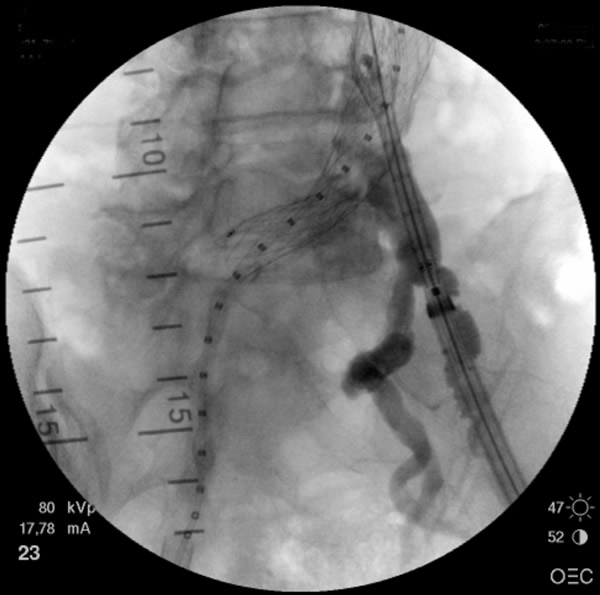

Figure 5: The stent graft is completely deployed and ballooned. Angiogram reveals patent bilateral renal and internal iliac arteries.

- After the deployment of the contralateral iliac limb (Figure 4), the surgeon will evaluate the need for further iliac limb extenders or aortic cuffs. It is important to cover the entire length between the lowest renal artery and the internal iliac artery. The stent grafts are subsequently ballooned as suggested by the IFU. An IVUS interrogation of the entire stent graft and surrounding aortic branches is performed. This will detect any circumferential stent mal-apposition to the proximal or distal landing zone that may lead to endoleak. A completion angiogram is performed to confirm lack of gross endoleak (Figure 5, Video 1, , “Completion angiogram” confirms the patency of both renal arteries and lack of proximal endoleak (type Ia).) However a single aortogram may miss endoleak due to projection overlap. A bi-plane aortogram is more reliable in excluding any significant procedural endoleak.